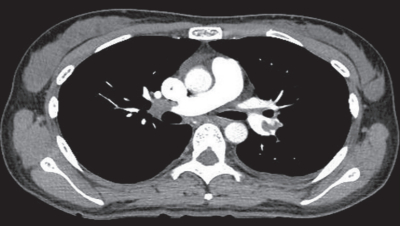

胸部造影 CTを別に示す。最も適切な治療薬はどれか。

a. ヘパリン

b. アスピリン

c. 血管拡張薬

d. 殺細胞性抗癌薬

e. 副腎皮質ステロイド